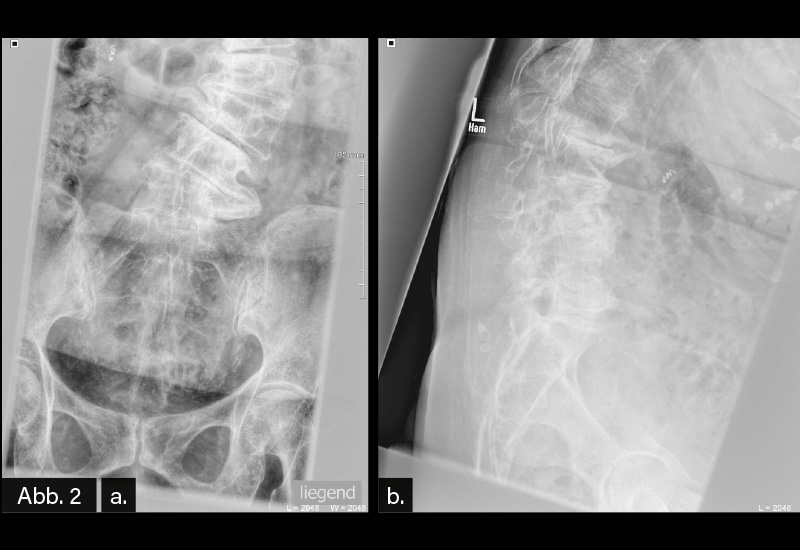

BILDGEBENDE DIAGNOSTIK: Röntgen (s. Abb. 1/ Abb. 2)

DIAGNOSE: Fortgeschrittene langjährige Torsionsskoliose mit Abstützungsreaktionen

Die Diagnose wird mit der konventionellen Röntgendiagnostik gestellt. Zur genauen Beurteilung ist eine Aufnahme der BWS und LWS (auch in Form einer Ganzwirbelsäulen-Röntgenaufnahme) im aufrechten Stand notwendig. Idealerweise werden zusätzlich die Beckenkämme zur Bestimmung des knöchernen Wachstumsstatus sowie die Schlüsselbeine zur Bestimmung des Schulterstandes abgebildet. Die Diagnose wird jedoch erst gestellt, wenn zusätzlich eine Rotationsabweichung besteht. Die seitliche Röntgenaufnahme vermittelt Informationen über das sagittale Profil. Die Abbildung des Beckens und der Hüftgelenke auf der seitlichen Röntgenaufnahme ermöglicht die Bestimmung der Wirbelsäulen-Becken-Relation. Das Becken besitzt bei sagittalen Wirbelsäulendeformitäten die Möglichkeit der kompensatorischen Rotation um die Oberschenkelköpfe, wodurch es zu einem Wiederaufrichten der Wirbelsäule kommt.